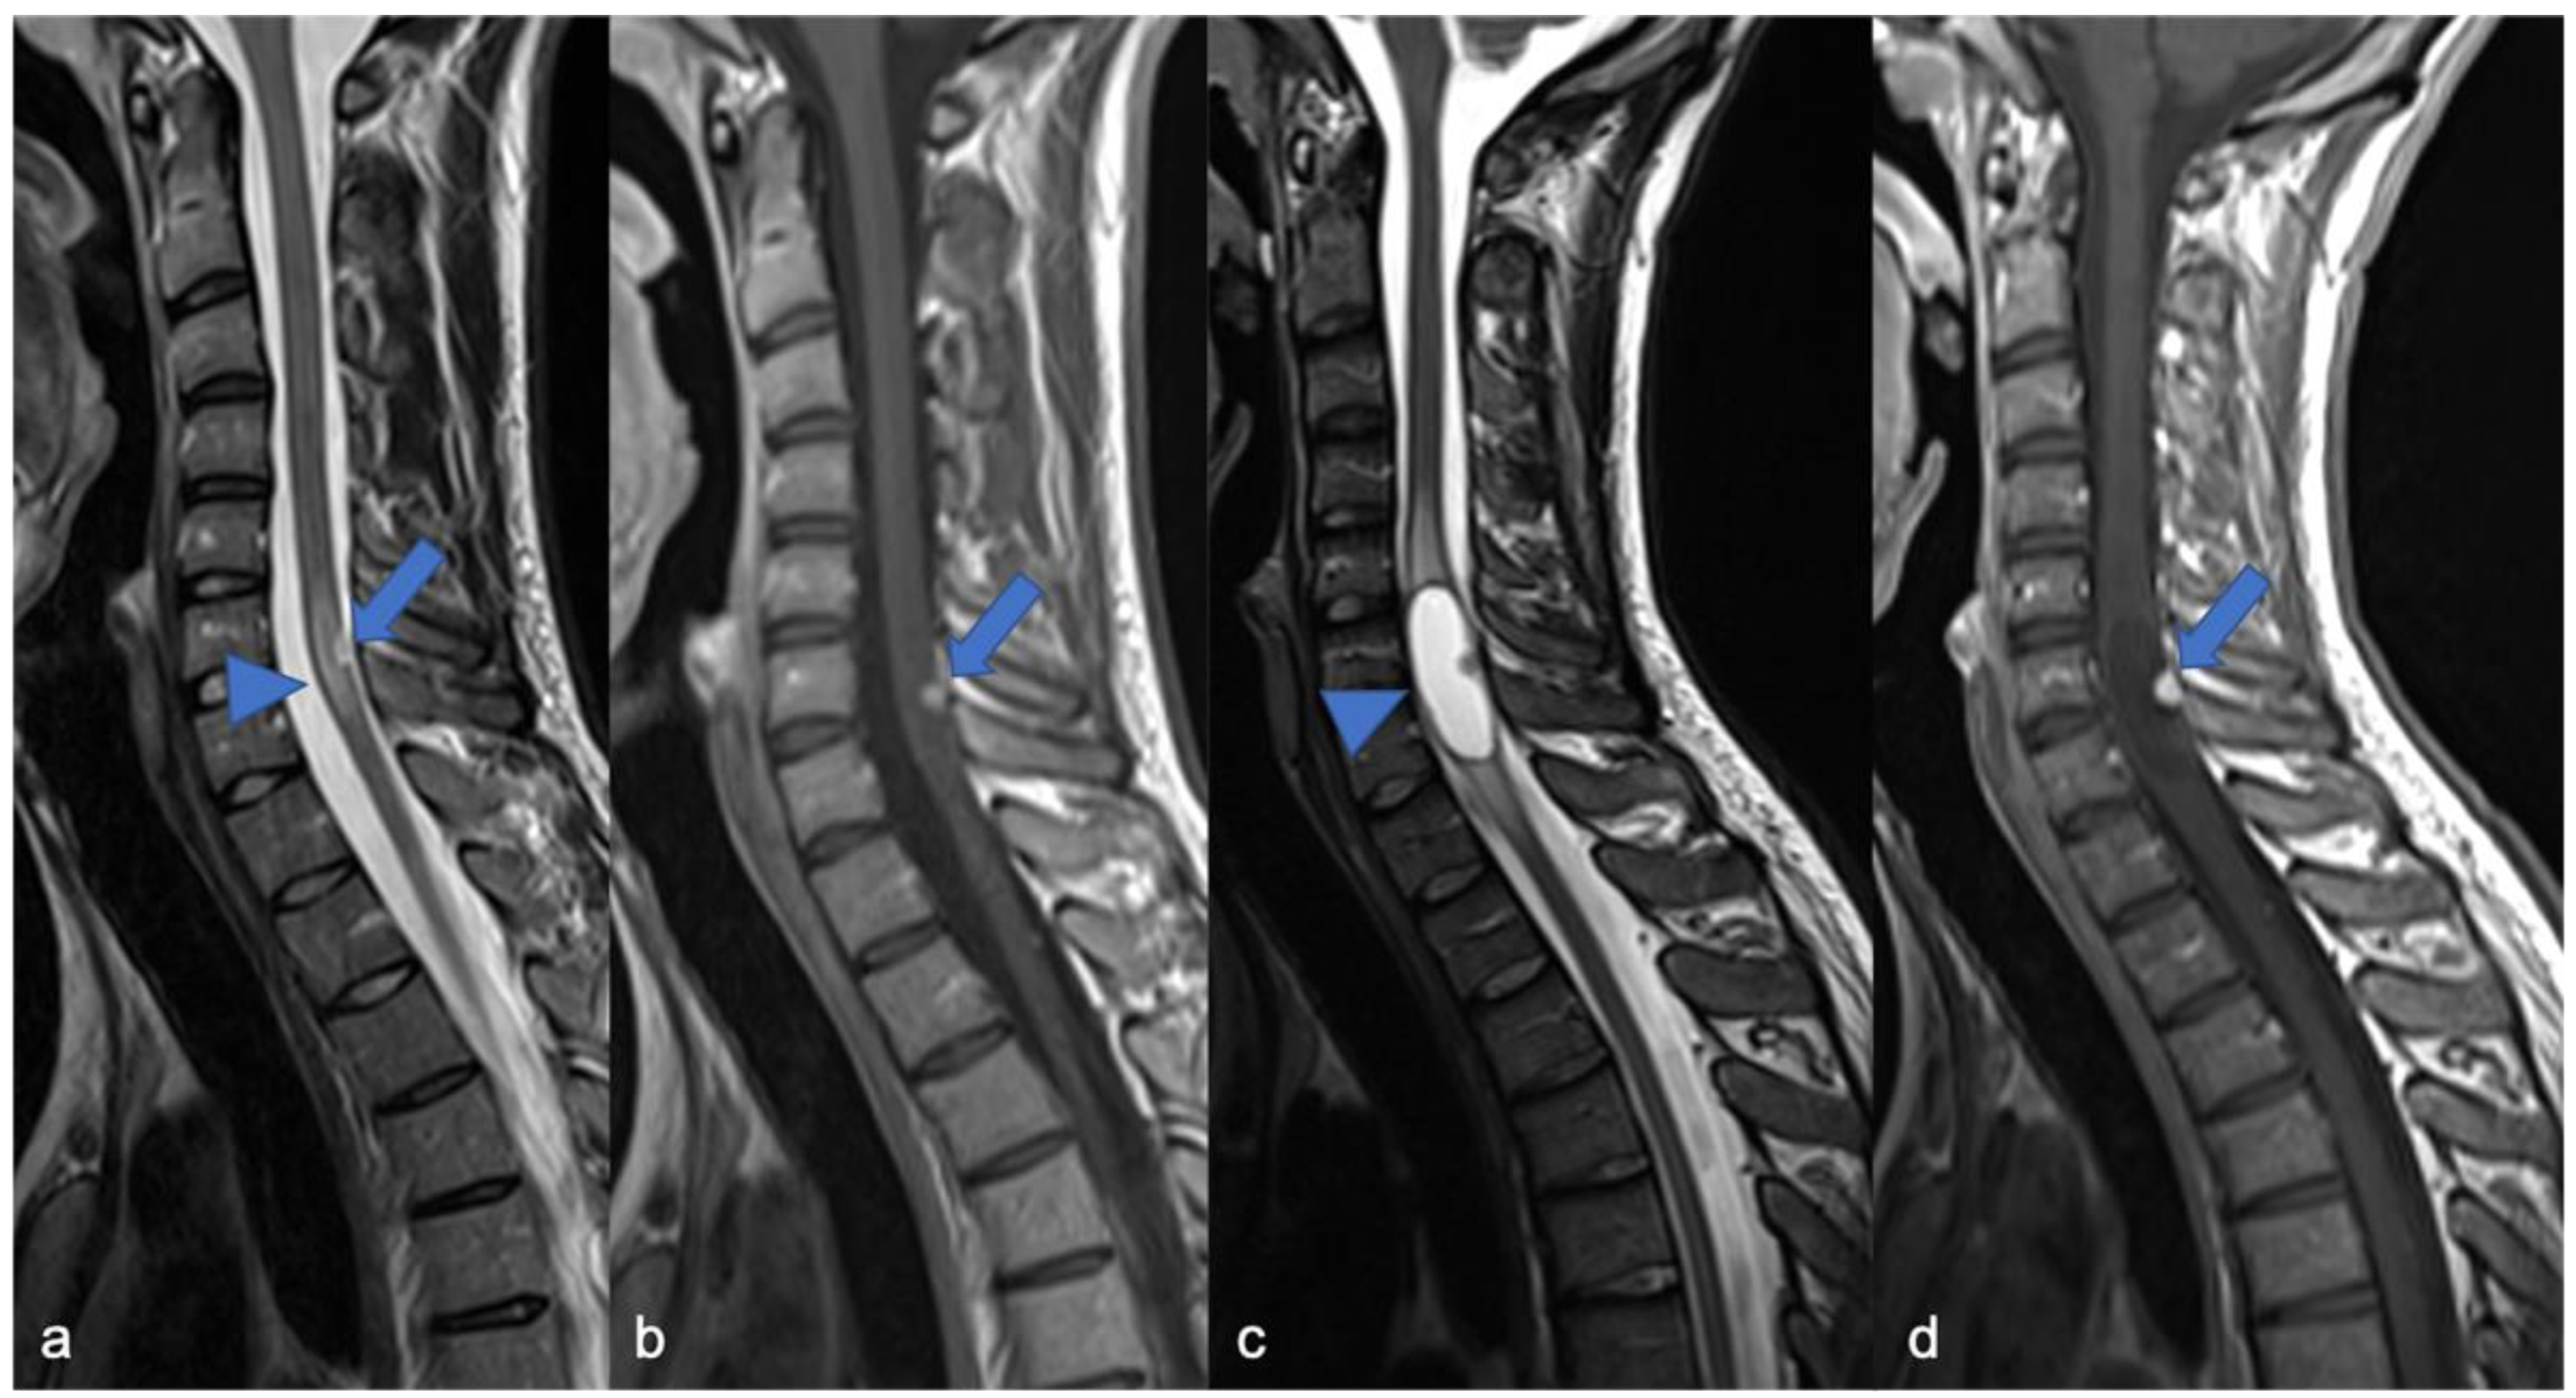

2. Gliomas and Mixed Neuronal–Glial Tumors

2.1. Gliomas